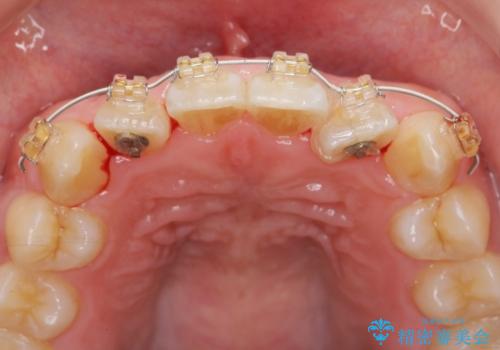

マウスピース矯正では改善の難しい前歯のねじれを前歯の部分ワイヤー矯正で改善したのち、インビザライン矯正を行い歯列を整えます。

インビザラインを行う前に前歯の部分矯正を行ったことで、しっかりとねじれが取れ整った歯列へと仕上げることが出来ました。